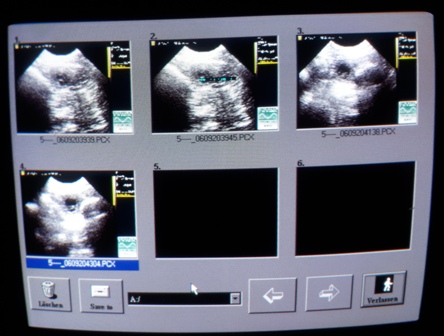

12.06.2021 - 24. Tag der Trächtigkeit

Der Ultraschall war so schön, Melli und ich konnten einige Lillis sehen :)

Herrlich!

Zählen unmöglich, ein normaler Wurf denke ich...

Das wird Überraschung bleiben!

Das Fotomachen war schwierig: Phoebe kraulen, schallen und knipsen war zu viel!

Immer wenn wir mal 3 gleichzeitig drauf hatten, war ein Atemzug später wieder alles weg ;)

Bin halt ein Laie, aber es geht ja auch nur darum zu wissen:

Juhuuu!!! Wir sind trächtig :) :)

Nun sind sie Realität, das ist sooo schön!